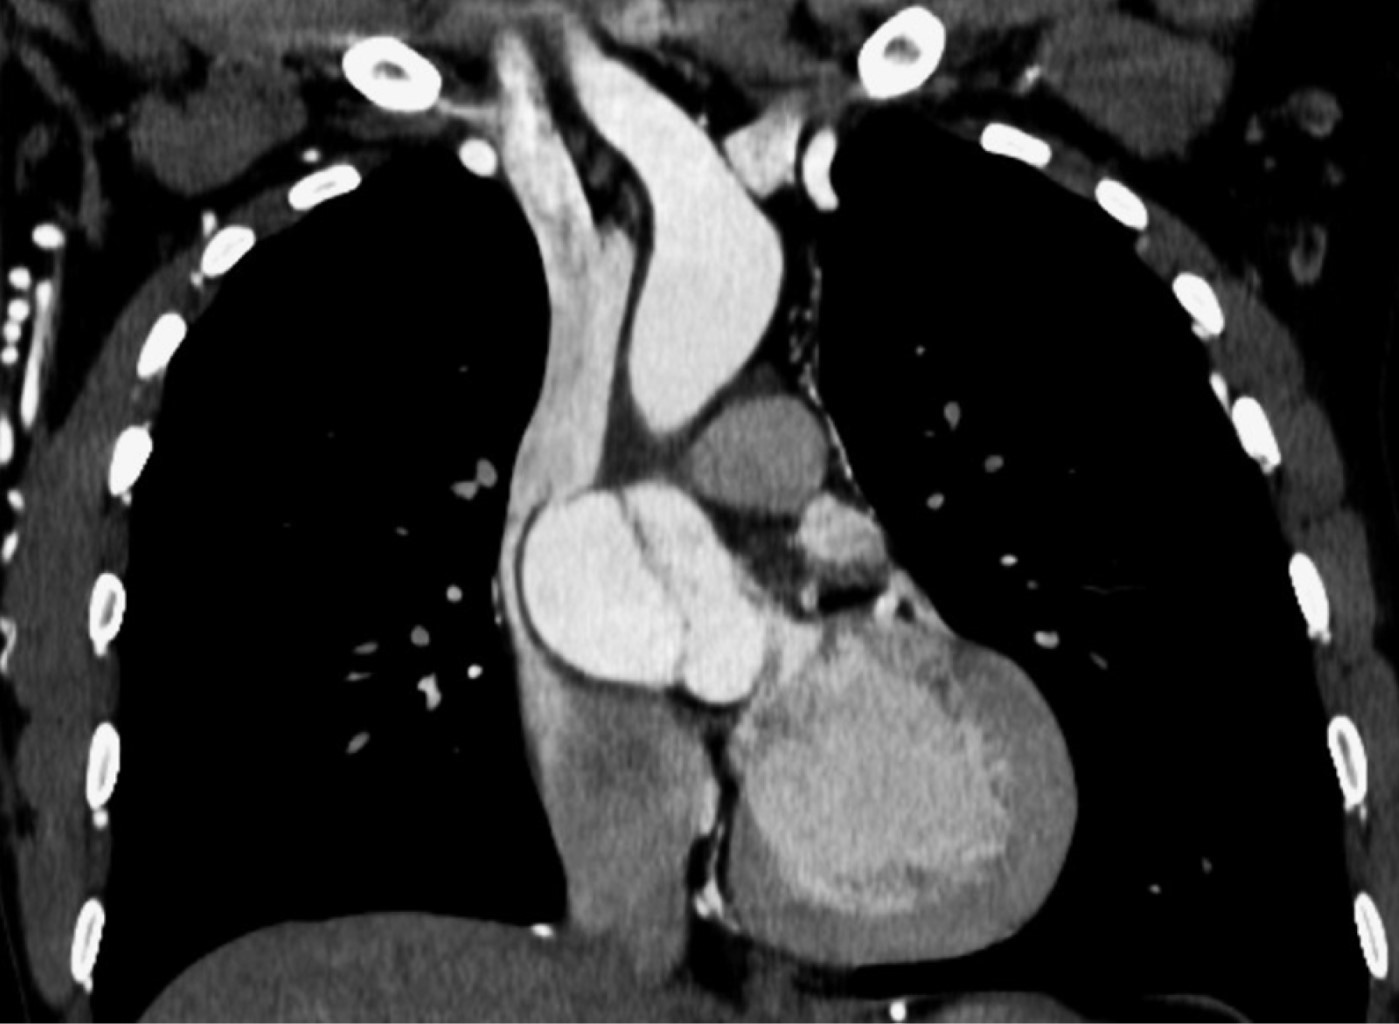

Coartación aórtica asociada a válvula aórtica bicúspide complicada con aneurisma aórtico postdisección

Sánchez-Amaya DJ, Godínez-Córdova LB, López-Lizárraga MÁ, Araiza-Garaygordobil D, Arias-Mendoza A

coartación aórtica, disección aórtica crónica, aneurisma aorta ascendente, válvula aórtica bicúspide.

La coartación aórtica es un trastorno congénito que afecta no solamente a la aorta, sino que también puede asociarse a válvula aórtica bicúspide y predispone a síndromes aórticos. Se reporta el caso de un paciente de 28 años de edad con hipertensión secundaria debido a coartación aórtica postductal asociada a válvula aórtica bicúspide que a su vez presentó disección crónica de la aorta ascendente. La coexistencia de enfermedad valvular aórtica, así como múltiples condiciones aórticas, es una situación rara que requiere una evaluación altamente especializada para garantizar un resultado favorable. El tratamiento se estableció en dos fases: aortoplastia con colocación de stent y luego cirugía de reemplazo aórtico y valvular, con una recuperación favorable.

Figura 3